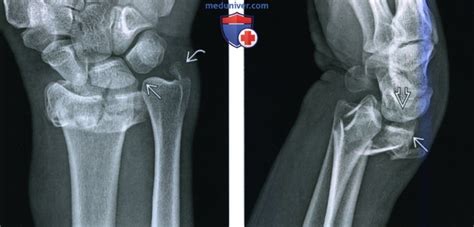

Рентгенограмма при переломе дистального эпимета...